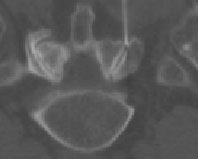

Thermokoagulation unter Computertomographie

Nach Injektion von Cortison mit Lokalanästhetikum und Kontrastmittel, in der Folgezeit (vorübergehend) deutliche Beschwerdebesserung, somit Indikation zur Thermokoagulation

Im Abstand von einigen Wochen, etwas dickere Nadel zur Thermokoagulation, punktgenau plaziert